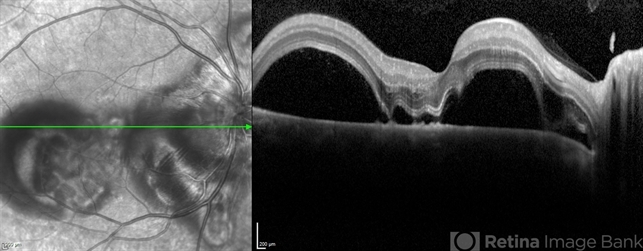

- Preeclampsia in a 30 YO

- preeclampsia, central scotoma, blurred vision

- Optical coherence tomography system

- A 30-year-old presented with central scotoma and blurred vision a day following C-section for preeclampsia.